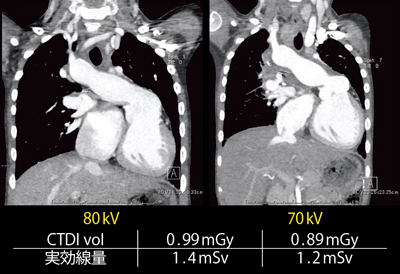

CARE kVにおける70kVと80kVの比較も行った(表1)。CARE kVはスカウトビューを撮影したところで管電圧が決定される。体重別では,10kg以下では70kVが選択される傾向があった。実効線量は,80kV 59例の平均が1.70mSv,70kV 167例の平均が1.44mSvであった。

1回目の撮影時に80kV,2回目に70kVになった6歳,女児の症例で,管電圧による画質の違いを比較してみた(図9)。管電圧が低いほど造影剤の吸収値が上昇するため,70kVの画像が好まれる場合もあるのではないかと思われた。

実効線量は,80kVでは1.4mSv,70kVでは1.2mSvだった。体重10kg以下の症例では,70kVのFlash Spiralで撮影しても,十分な高画質が得られることがわかった。Definition Flashによる小児の心臓CTは,1人あたりの自然放射線の世界平均年間被ばく線量である2.4mSvに比べても,非常に低い被ばく線量で撮影することが可能である。

![]() 表1 管電圧による被ばく線量の比較 |

![]() 図9 管電圧70kVと80kVの画像の比較 6歳,女児,肺動脈閉鎖,心室中隔欠損,MAPCAs rt Unifocalization後,bil m-BTシャント後 |